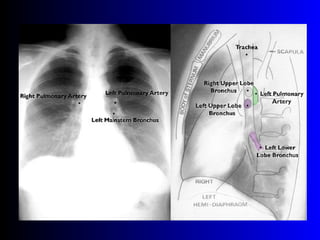

Este documento describe la técnica para realizar una telerradiografía de tórax normal e identifica las estructuras visibles en la imagen, incluyendo los huesos, vasos sanguíneos, grasa, tejido subcutáneo, pulmones y mediastino. Explica que es importante centrar la imagen en los ápices pulmonares, senos costodiafragmáticos e inspiración profunda para una visión clara de las estructuras.